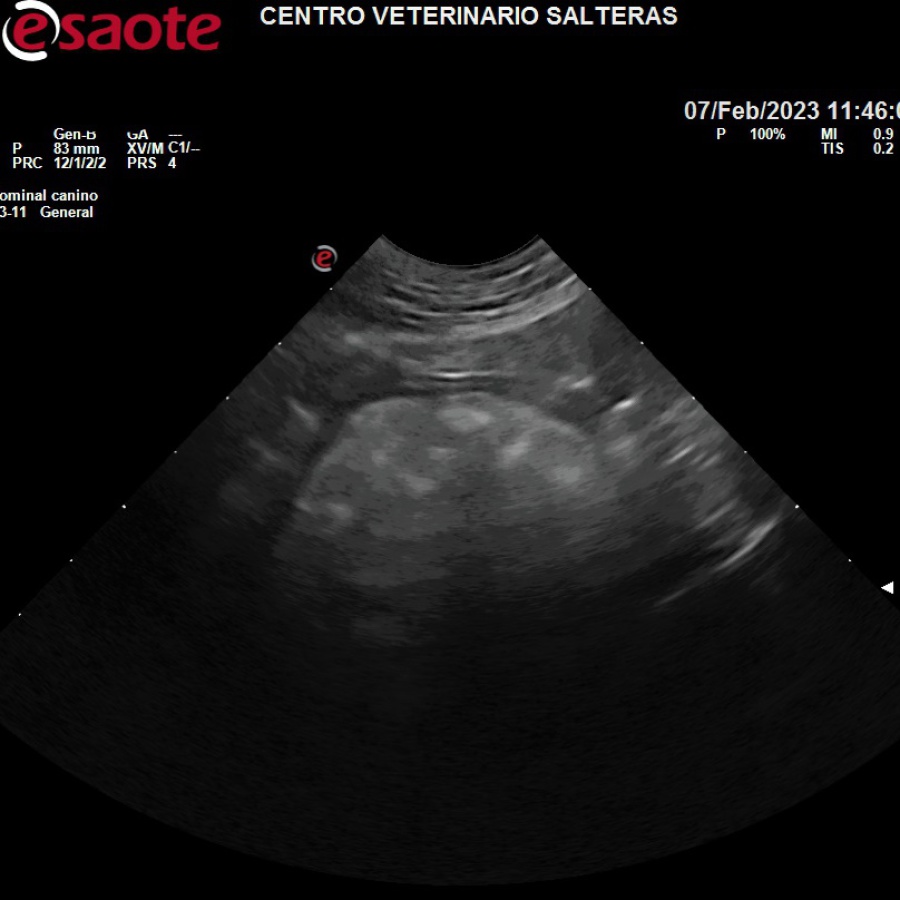

La ecografía es un método diagnóstico no invasivo que permite visualizar en tiempo real el estado interno de los órganos, así como su movimiento y dimensiones. Por tanto, podemos tambien observar alteraciones en dichos órganos, como la presencia de tumores, patologías y pérdida de definición estructural, permitiendo en muchas ocasiones llegar a un diagnóstico definitivo.

En hembras gestantes permite visualizar los fetos, sus latidos y comprobar su estado a partir de los 30 días de gestación.

Nuestro equipo es de última generación, por lo que permite además la visualización de flujos de sangre (ecografía Doppler). Esto es especialmente útil en lesiones que producen cambios de presiones vasculares, como pueden ser algunas patologías hepáticas o renales.

Es de vital importancia ante urgencias por traumatismo, como atropello o pelea con otro perro, ya que se puede diagnósticar rápidamente la rotura de órganos vitales, como la vejiga urinaria o el bazo.